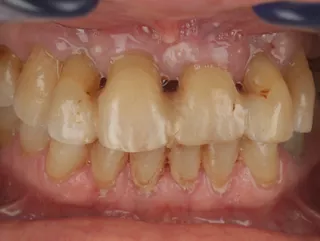

Guided FP1 maxillary rehabilitation with Straumann® STARconcept™ and Straumann iGuide™. A clinical case report by Dr. David Norré, Belgium.

Facially driven Smilecloud design with a focus on preserving tissue and bone. Planned in Smile in a Box and executed with the iGuide protocol; shared pin positions align the drill and prosthetic guides for chairside pickup of the pre-designed provisional. Day-5 follow-up shows the screw-retained provisional in place.

• Pre-operative smile.

• Initial clinical situation (retracted view).